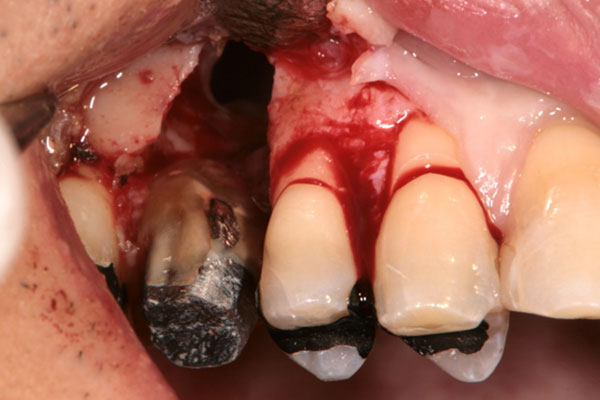

歯周病が進行して、歯の根元まで炎症が広がることがあります。右の写真をご覧ください。赤丸で囲んだ分が黒くなっています。ここは、歯肉が衰え、歯と歯肉の間にできたすき間です。ここに付着した歯石を取り除くことはできません。放置すると歯周病がさらに進行して、やがて抜歯となってしまうでしょう。

そこで、外科的手術で歯の根を露出させて歯石を取り除きます。さらに歯の根の間に歯間ブラシが入るように穴をあけ、お手入れしやすくします。この術式を「トンネリング」といいます。